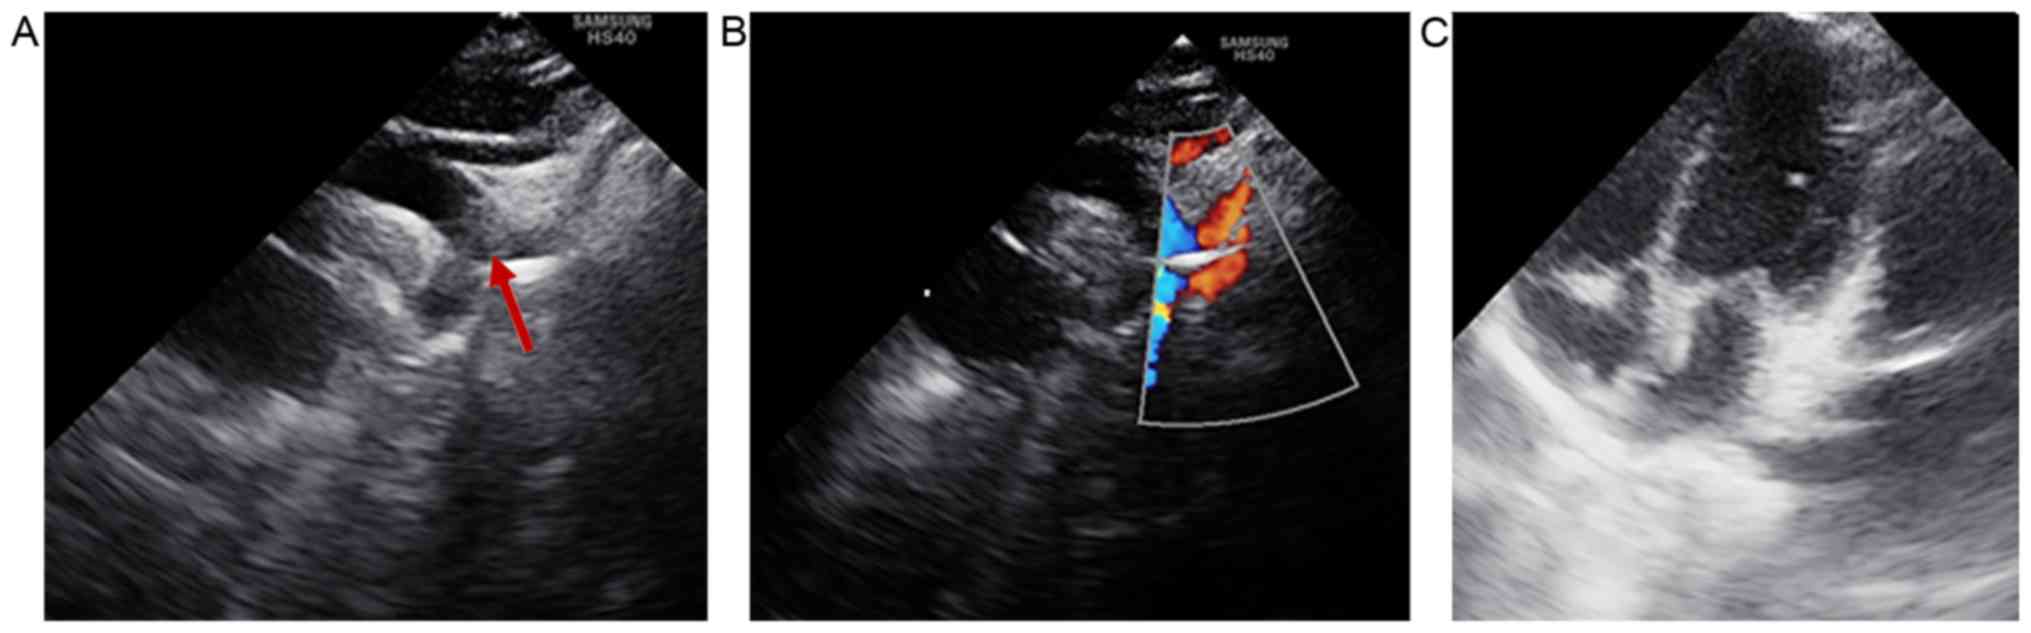

Heart ultrasonography revealed that the patient did not display any intracardiac structural abnormalities; therefore, the only cardiac defect identified that was associated with CHARGE syndrome was the aberrant origin of the right subclavian artery (Fig. 4).

Figure 4

Heart ultrasonography. (A) The suprasternal window displays the left-sided aortic arch with the aberrant origin of the right subclavian artery (arrow), which arises from the proximal part of the descending aorta. (B) The suprasternal window with color Doppler flow displays the left-sided aortic arch with flow across the aberrant right subclavian artery (arrow), right common carotid artery and left subclavian artery. (C) Apical four-chamber window displaying normal cardiac structures.